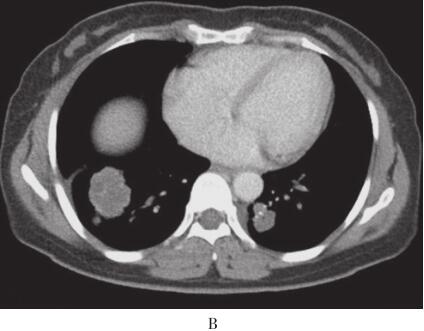

入院后体查未见阳性体征。辅助检查结果:血脂:甘油三酯为0.87mmol/L,总胆固醇为3.44mmol/L,高密度脂蛋自为0.85mmol/L,低密度脂蛋自为2.31mmol/L。ESR为29mm/ h。PPD试验及结核抗体阴性。血癌胚抗原(CEA)为0.6μg/ml。胸部增强CT示右下肺肿块约3.5cm×3.2cm,边缘呈分叶状,密度尚均匀,平扫CT值14HU,增强后30HU,双肺内还可见多个散在小结节影,左肺较大结节约1.5cm×2.0cm,边缘清晰,纵隔内未见肿大淋巴结(图1)。支气管镜检查示支气管炎症。痰及BALF未见异常细胞。入院后第1次CT引导下经皮右肺肿块穿刺活检病理示慢性炎症、纤维组织增生,可见胆固醇结晶沉积、富含脂质的巨噬细胞及较多空泡状细胞,上皮标记阴性,未见肿瘤细胞。全身PET/ CT显示右下肺前基底段团块状异常放射性浓聚影(3.2cm×4.2cm×3.5cm,最大SUV为6.4),双肺散在多个大小不等结节影,最大者位于左下肺后基底段,长径约2.2cm,最大SUV为3.8。第2次右下肺肿块穿刺活检,病理结果基本同前,病变符合外源性脂质性肺炎。

图1 2010年12月2日胸部增强CT

右肺肿块,双肺多发结节